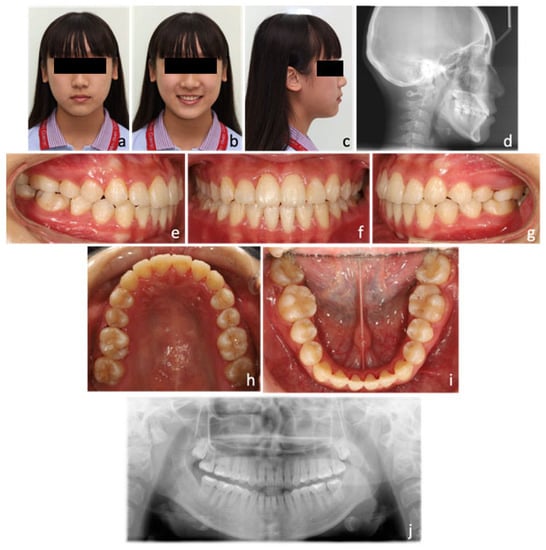

| Norm. | Initial | Post-Expansion | Final | |

|---|---|---|---|---|

| Skeletal analysis | ||||

| SNA | 82+/−2° | 83 | 84 | 83.5 |

| SNB | 80+/−2° | 83 | 82 | 82 |

| ANB | 2+/−2° | 0 | 2 | 1.5 |

| SN-MP (Go-Gn) | 32+/−5° | 34.5 | 35.5 | 35 |

| Frankfort-mandibular angle (FMA) | 25+/−5° | 29.8 | 32 | 31 |

| Dental analysis | ||||

| U1-NA (mm) | 3.18~7.34 mm | 5.8 | 6.6 | 6.1 |

| U1-SN | 102.23~115.13° | 108 | 112 | 115 |

| L1-NB (mm) | 3.18~7.34 mm | 5.8 | 5.5 | 6.1 |

| L1-MP (Go-Gn) | 90.56~103.12° | 87 | 87 | 91 |

| Facial analysis | ||||

| E-line (U) | −2.93~0.41 mm | −3.5 | −1.6 | −1.1 |

| E-line (L) | −1.86~2.1 mm | 0 | 0 | 0 |

| Facial convexity (G-Sn-Pg’) | 4.34~15.84° | 7.2 | 10.5 | 8.2 |